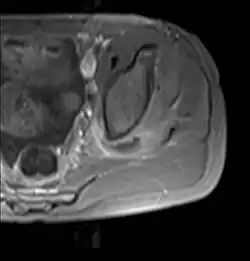

Axial T1 weighted fat suppressed post IV gadolinium contrast enhanced MRI image showing a mutliloculated bacterial abscess in the left gluteal muscle which grew Staphylococcus aureus (methicillin sensitive) thought to be due to tropical pyomyositis.